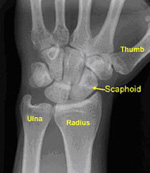

Similarly, an unrecognized (occult) fracture may be mistakenly considered a mild or moderately sprained wrist. If left untreated, the broken bone may not heal and will require a surgery that could have been avoided with early, appropriate treatment. The most common example of this is an occult fracture of the scaphoid bone.

X-rays. Although they will not show an injury to the ligament, x-rays can show whether the injury is related to a broken bone.

Many ligaments support the wrist.